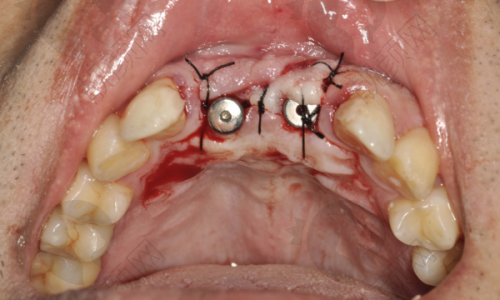

许士强医生在全口半口种植领域有着出色的水平。他具备丰富的临床经验,能够熟练运用多种精良的种植技术,如VIIV穿翼、下颌跨神经、内提升、外提升等,为患者制定个性化的种植方案。在面对骨量不足等复杂情况时,他也能凭借专精的技术和丰富的经验,成功完成种植手术,确保种植体的稳定性和成功几率。他的技术得到了业界的认可和患者的好评,是一位值得信赖的口腔种植骨干医生。

许士强医生从事口腔医疗工作11年,积极参与口腔技能培训及学术交流会议,不断提升自己的专精水平。他在工作中积累了丰富的临床经验,尤其在全口半口种植、VIIV穿翼、下颌跨神经、内提升、外提升、牙周序列治疗、智齿拔除等方面有着深入的研究和不错的技术。他凭借专精的知识和良好的医德,赢得了患者的广泛赞誉。

曾有一位老年患者,全口牙齿缺失多年,生活受到了极大的影响。患者来到上海鼎植口腔找到许士强医生,希望能够解决牙齿缺失的问题。许医生经过详细的检查和评估,为患者制定了全口半口种植方案。在手术过程中,许医生凭借不错的技术和丰富的经验,顺利完成了种植手术。术后,患者修复良好,牙齿功能得到了极大的改善,生活质量也得到了显著提高。患者对许医生的技术和服务非常满意,称赞他是一位医术高超、职责心强的好医生。